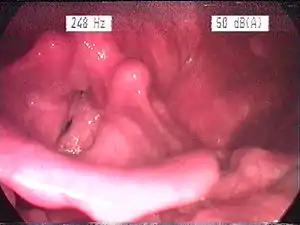

| Endoscopic image of an inflamed larynx caused by acid reflux | |

The larynx itself will often show erythema (reddening) and edema (swelling). This can be seen with laryngoscopy or stroboscopy (method depends on the type of laryngitis).[7]: 108 Stroboscopy may be relatively normal or may reveal asymmetry, aperiodicity, and reduced mucosal wave patterns.[22]